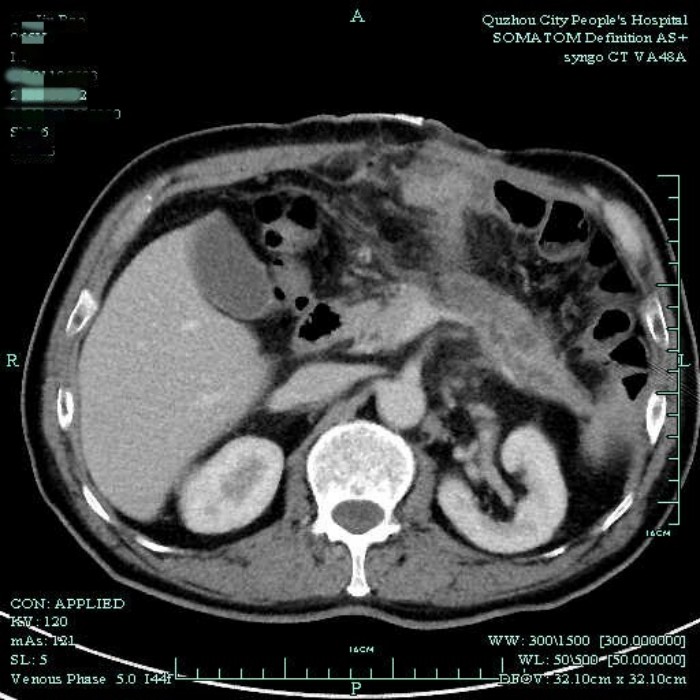

通過電話溝通,醫(yī)生在了解病情后,建議余大伯早點(diǎn)到醫(yī)院治療。入院后,醫(yī)生檢查發(fā)現(xiàn)余大伯腹壁引流管縫隙處已經(jīng)糜爛,形成潰瘍,這是因?yàn)殚L期縫線的牽拉,加上大量的胰液滲漏腐蝕管口的新生組織造成。后來通過CT檢查,發(fā)現(xiàn)胰尾處有一個巨大囊腫,綜合考慮患者病情后,建議盡早手術(shù)治療。